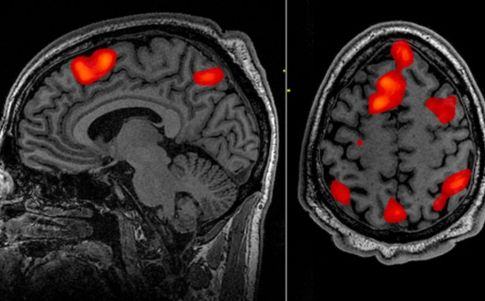

El miedo es una respuesta adaptativa de la que disponemos para sobrevivir. A nivel cerebral, esta respuesta se traduce en una actividad neural coordinada de tres áreas: el hipocampo, la corteza prefrontal medial (CPFm) y la amígdala.

Borgomaneri y la coautora del estudio Simone Battaglia utilizaron la TMS (estimulación magnética transcraneal) para “borrar” el miedo inducido por un recuerdo negativo. Se trata de un procedimiento no invasivo, no requiere cirugía ni acción alguna sobre el participante. De este modo, aplicaron el nuevo protocolo sobre un grupo de 98 personas sanas. Todos los participantes habían aprendido una memoria negativa y, al día siguiente, fueron sometidos a una sesión de TMS sobre su corteza prefrontal. “Gracias a este procedimiento, obtuvimos resultados que hasta ahora solo eran posibles mediante medicamentos”, aseguró Sara Borgomaneri.

El enfoque principal es lo que llaman proceso de reconsolidación. Este proceso mantiene, fortalece y altera eventos que ya están almacenados en nuestra memoria a largo plazo. En opinión de Battaglia, cada vez que recordamos un acontecimiento, hay un período de tiempo limitado en el que puede modificarse nuestra memoria. Lo que hace el protocolo es aprovechar esta breve ventana de tiempo e interferir en los recuerdos aversivos aprendidos. “Primero, creamos la memoria aversiva combinando una estimulación desagradable con algunas imágenes. Al día siguiente, presentamos a un grupo de participantes con el mismo estímulo, que, en su memoria, se registró como aversivo. Usando TMS inmediatamente después, interferimos con su actividad de corteza prefrontal”, explica Borgomaneri en el trabajo.